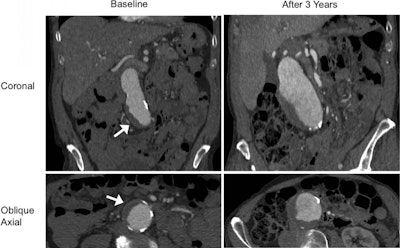

In the current study, Zhu and colleagues discovered that the diameter and presence of a blood clot on the MRI or CT scans of AAA patients were independently associated with statistically significant increases in aneurysm growth rate (p < 0.001; p = 0.02).

To be specific, the overall growth rate of AAAs in patients with an intraluminal thrombus was 2 mm per year -- double the 1-mm per year growth rate of AAAs in patients who did not have a blood clot on CT or MRI (p < 0.001). For small AAAs (3 cm to 4 cm), the growth rate was 1.9-fold faster in patients with a blood clot than in those without one. For medium AAAs (4 cm to 5 cm), the growth rate was 1.2-fold faster in those with a blood clot.